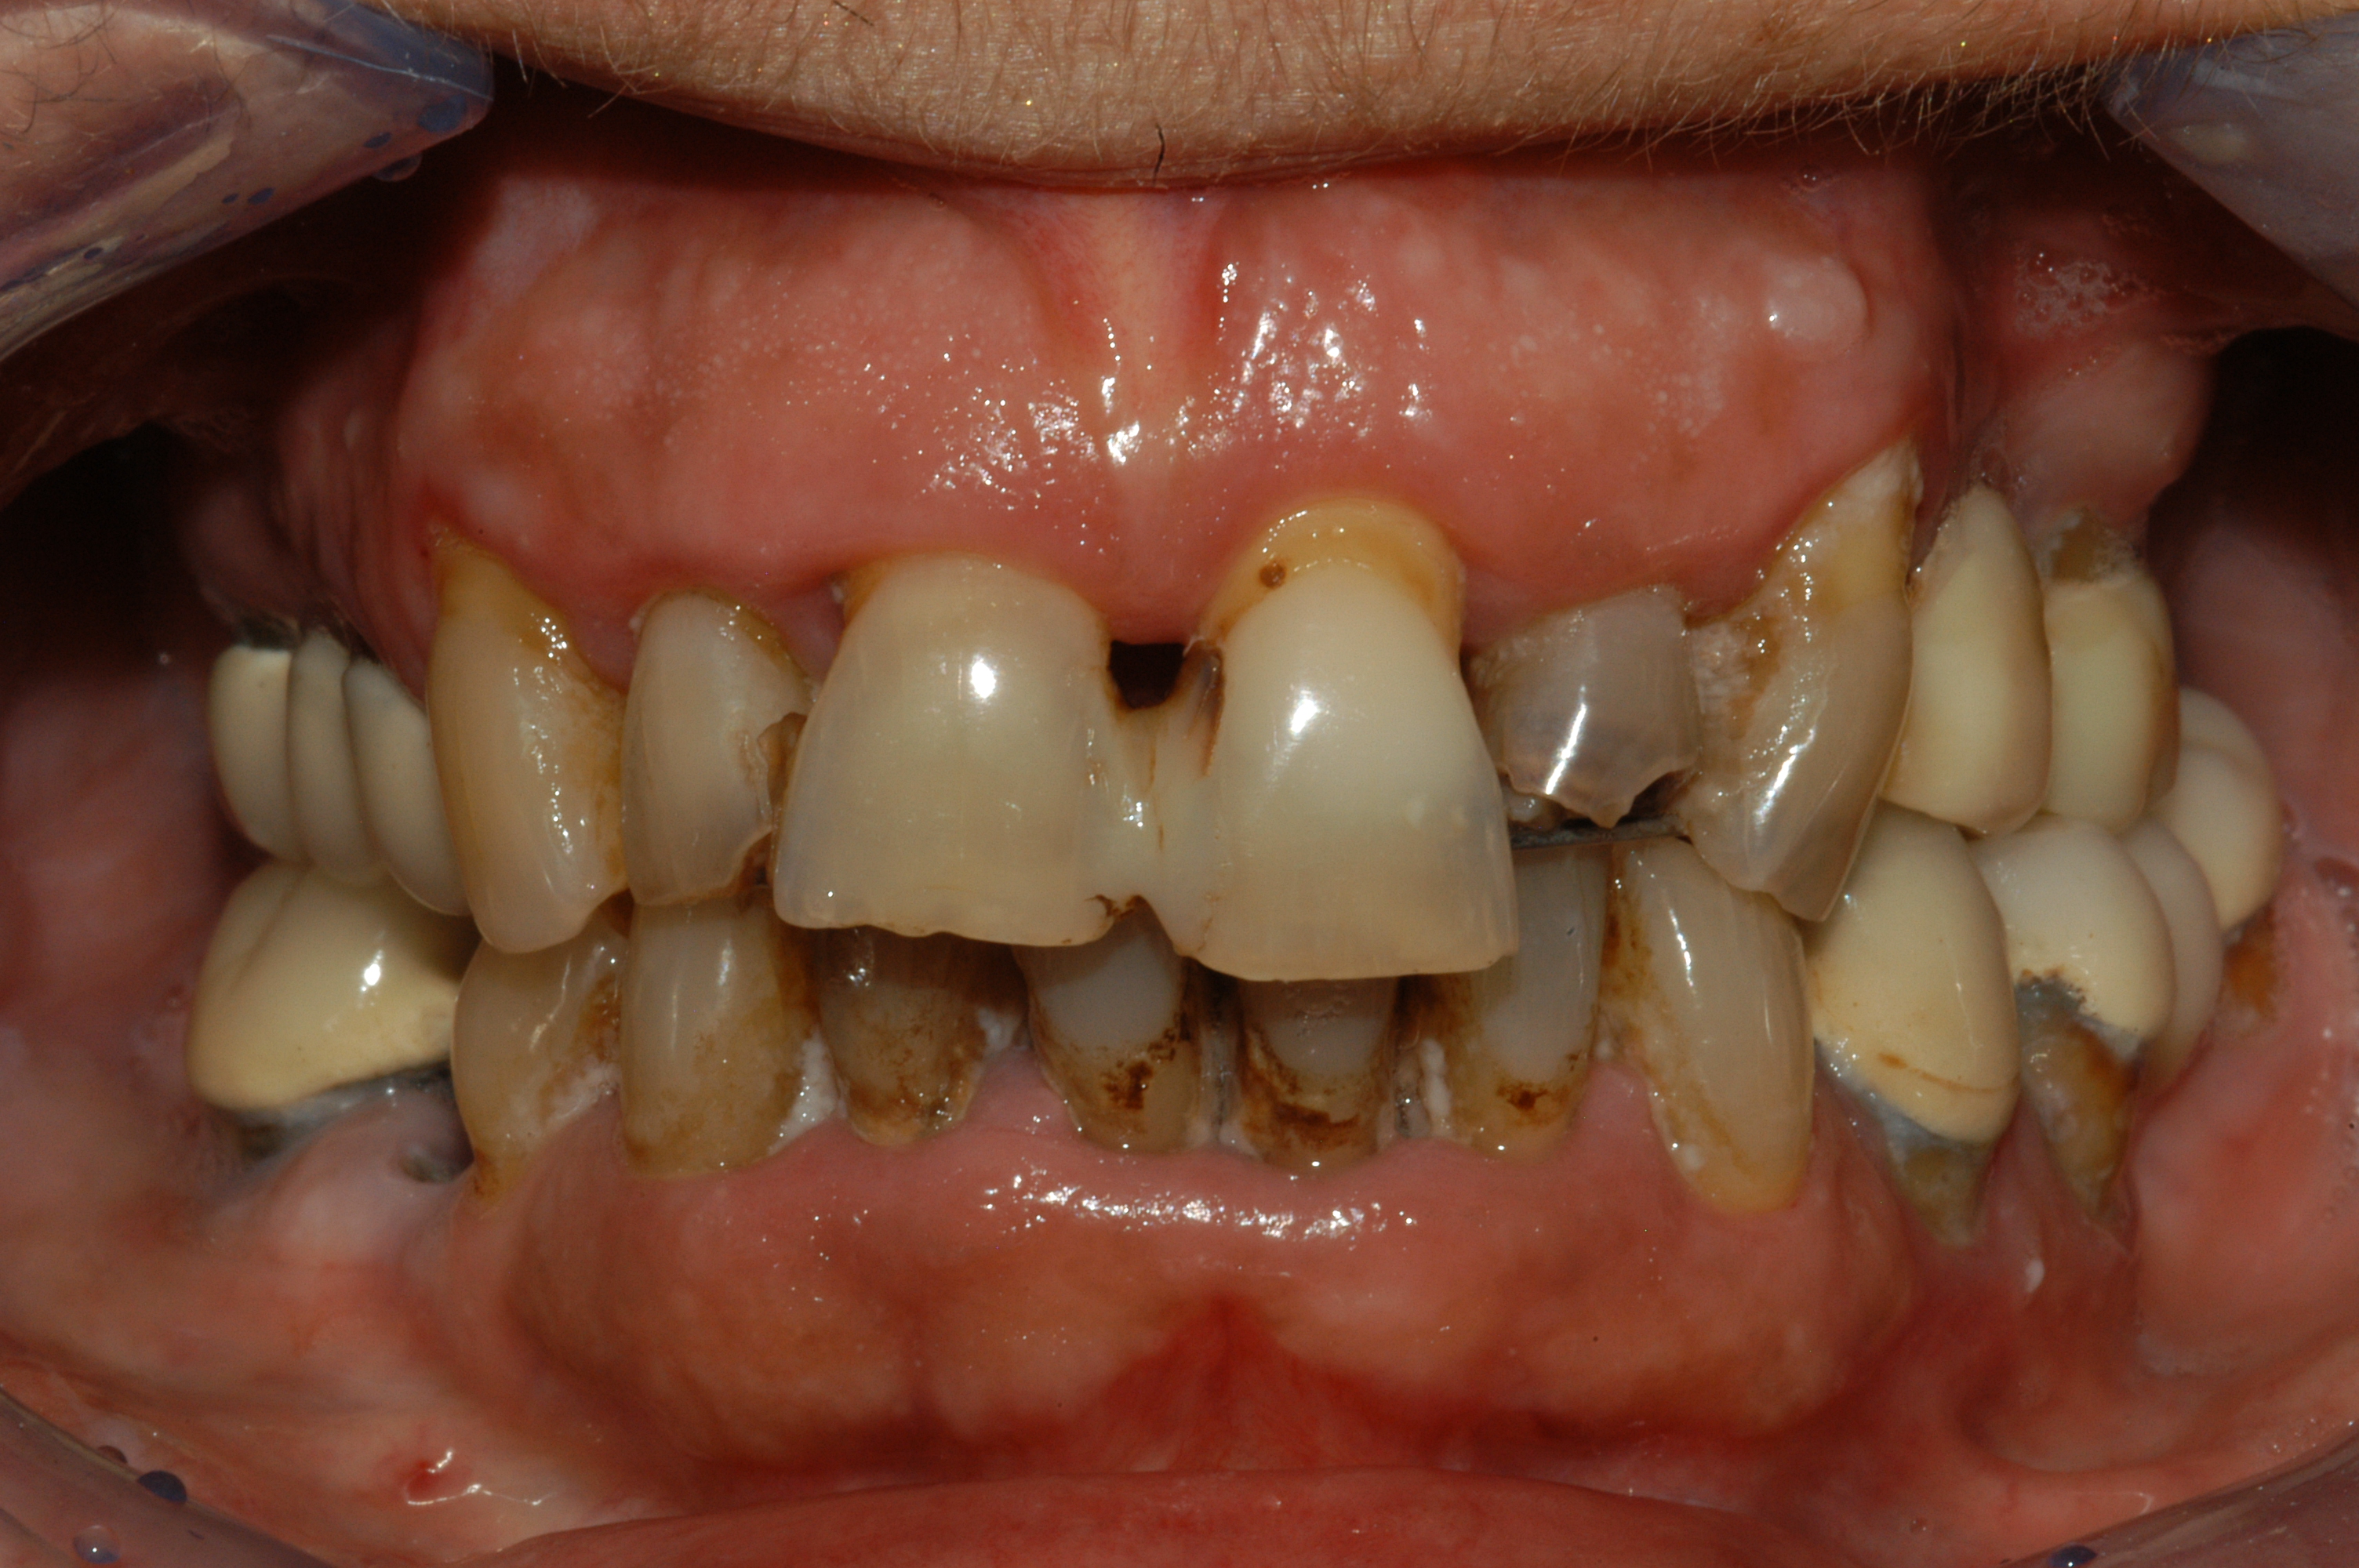

Riabilitazione completa superiore e settori posteriori inferiori

Paziente F, 52 anni, riabilitazione implanto-protesica completa superiore, ad appoggio dentale ed implantare. Riabilitazione implanto-protesica dei settori postero-laterali inferiori su denti naturali e su impianti.